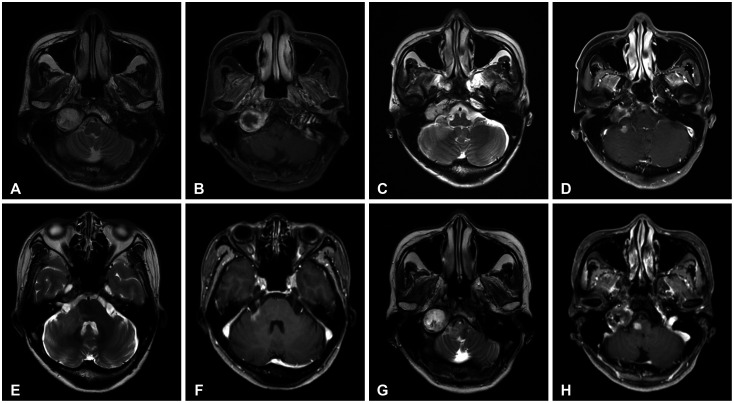

- Delayed cerebral necrosis is a well-known complication of radiation therapy (RT). Because of its irreversible nature, it should be avoided if possible, but avoidance occurs at the expense of potentially compromised tumor control, despite the use of the modern advanced technique of conformal RT that minimizes radiation to normal brain tissue. Risk factors for radiation-induced cerebral necrosis include a higher dose per fraction, larger treatment volume, higher cumulative dose, and shorter time interval (for re-irradiation). The same principle can be applied to proton beam therapy (PBT) to avoid delayed cerebral necrosis. However, conversion of PBT radiation energy into conventional RT is still short of clinical support, compared to conventional RT. Herein, we describe two patients with excessively delayed cerebral necrosis after PBT, in whom follow-up MRI showed no RT-induced changes prior to 3 years after treatment. One patient developed radiation necrosis at 4 years after PBT to the resection cavity of an astroblastoma, and the other developed brainstem necrosis that became symptomatic 6 months after its first appearance on the 3-year follow-up brain MRI. We also discuss possible differences between radiation changes after PBT versus conventional RT.